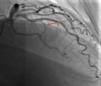

Case reportWe describe the case of a 73-year-old woman with acromegaly due to a pituitary adenoma diagnosed and treated surgically at the age of 38 but with recurrence and reoperation at the age of 50. She had a history of hypertension, multinodular goiter and atrial fibrillation under oral anticoagulation. She was referred to our cardiology department due to echocardiographic evidence of obstructive hypertrophic cardiomyopathy and a three-month history of progressively worsening exercise-induced dyspnea and orthopnea (NYHA class III) under optimal medical therapy. A complete echocardiogram revealed severe asymmetric hypertrophy of the left ventricle, mostly in the basal portion of the interventricular septum (19 mm), without LV dilation, depressed ejection fraction or wall motion abnormalities. There was also a dynamic LVOT obstruction gradient of 70 mmHg at rest and of 120 mmHg with Valsalva maneuver and systolic anterior movement (SAM) of the mitral valve with mild regurgitation and moderate to severe tricuspid regurgitation. A better characterization with magnetic resonance imaging confirmed basal interventricular septal hypertrophy without evidence of intramyocardial fibrosis (Figure 1). Genetic testing excluded the most frequent forms of familial hypertrophic cardiomyopathy. A 24-hour Holter examination revealed permanent atrial fibrillation but no ventricular repolarization or heart rate abnormalities. After a multidisciplinary discussion, ASA was performed, guided by myocardial contrast echocardiography, with injection of 2 cc of alcohol in the first septal branch of the left coronary artery (Figures 2–4). The procedure was uneventful and no atrioventricular (AV) conduction disturbances were detected. The one-year echocardiographic reassessment showed a reduction of the interventricular septum to 13 mm and of 8 mm in the region treated by ASA. The LVOT gradient was 28 mmHg at rest and the SAM of the mitral valve and the moderate to severe tricuspid regurgitation had disappeared. The patient improved significantly to mild-to-moderate heart failure (NYHA class I-II) and no major cardiovascular events were observed during follow-up.